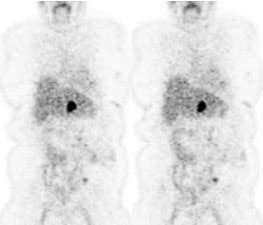

Initial staging for extrahepatic metastases: The patient below underwent FDG PET imaging to assess for extrahepatic metastatic disease prior to definitive surgical intervention. The PET exam demonstrates uptake within two hepatic metastases (black arrows on PET scan and yellow arrows on CT images) and in the patients primary colon cancer (blue arrow on PET scan and white arrow on CT image). No other sites of abnormal tracer uptake were identified which supports surgical intervention in this case. |